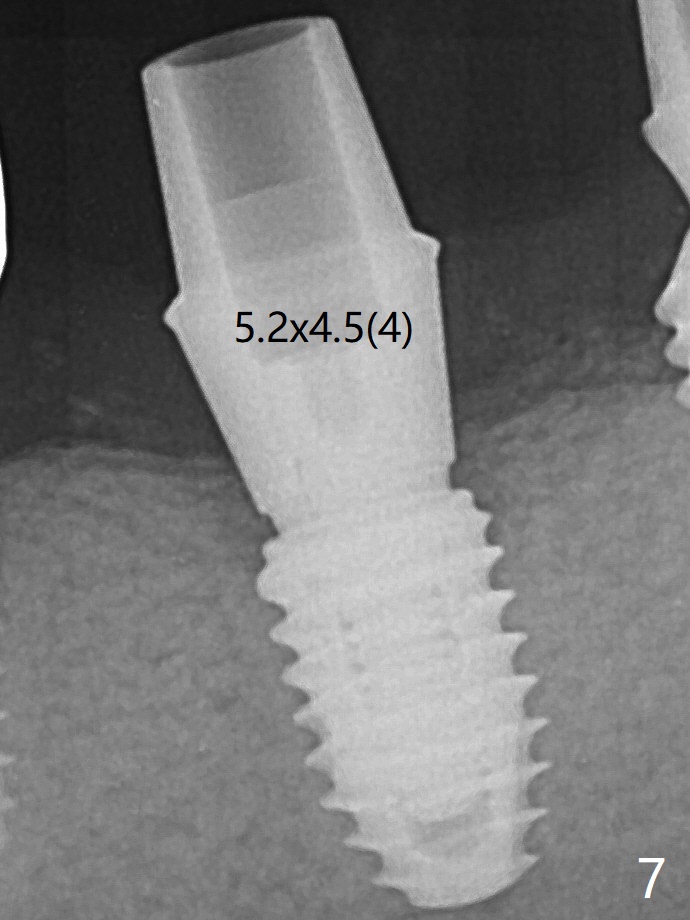

Since there is ~ 2 mm bone apical to the 5x8 mm loose implant at #19 (Fig.1), primary stability is achieved for a 4.5x10 mm dummy IS implant (having better surface treatment than the previous implant) when osteotomy is finished with a 4 mm drill (Fig.2). It is the same associated with a 4.5x7.3 mm definitive one with apical space (Fig.3 *). After depth adjustment to make sure that the implant is subcrestal circumferentially, sticky bone is placed on the top of the implant and around the implant at #18 (Fig.4 *), followed by PRF membranes and suturing with 5-0 PGA and 4-0 Chromic gut suture. Periodontal dressing is applied around the cemented abutment at #18 for additional retention. There is no paresthesia postop. In fact immediate implant redo is fairly safe. The wound heals 1 month postop (Fig.5). There is reorganized bone coronal to the healing screw 4 months postop (Fig.6), which is confirmed in uncovering. One month post uncover, the 6x4 mm healing abutment is found to be loose, suggesting incomplete seating after uncover. A 5.2x4.5(4) mm cemented abutment seems to be incompletely seated (Fig.7). It remains the same after 5.5 and 6.0 mm profile drills (Fig.8,9). A 4.5x4.5(4) mm abutment appears to be completely seated (Fig.10). When the crowns of #18 and 19 are cemented, the gingival embrasure between them is narrow (Fig.11 ^) because of bulky porcelain build-up (*). The tooth #21 with buccal Class V defect (Fig.12 *) seems to have occlusal trauma 1 year 6 months post cementation of #18 and 19. The problems are subsequently taken care of.